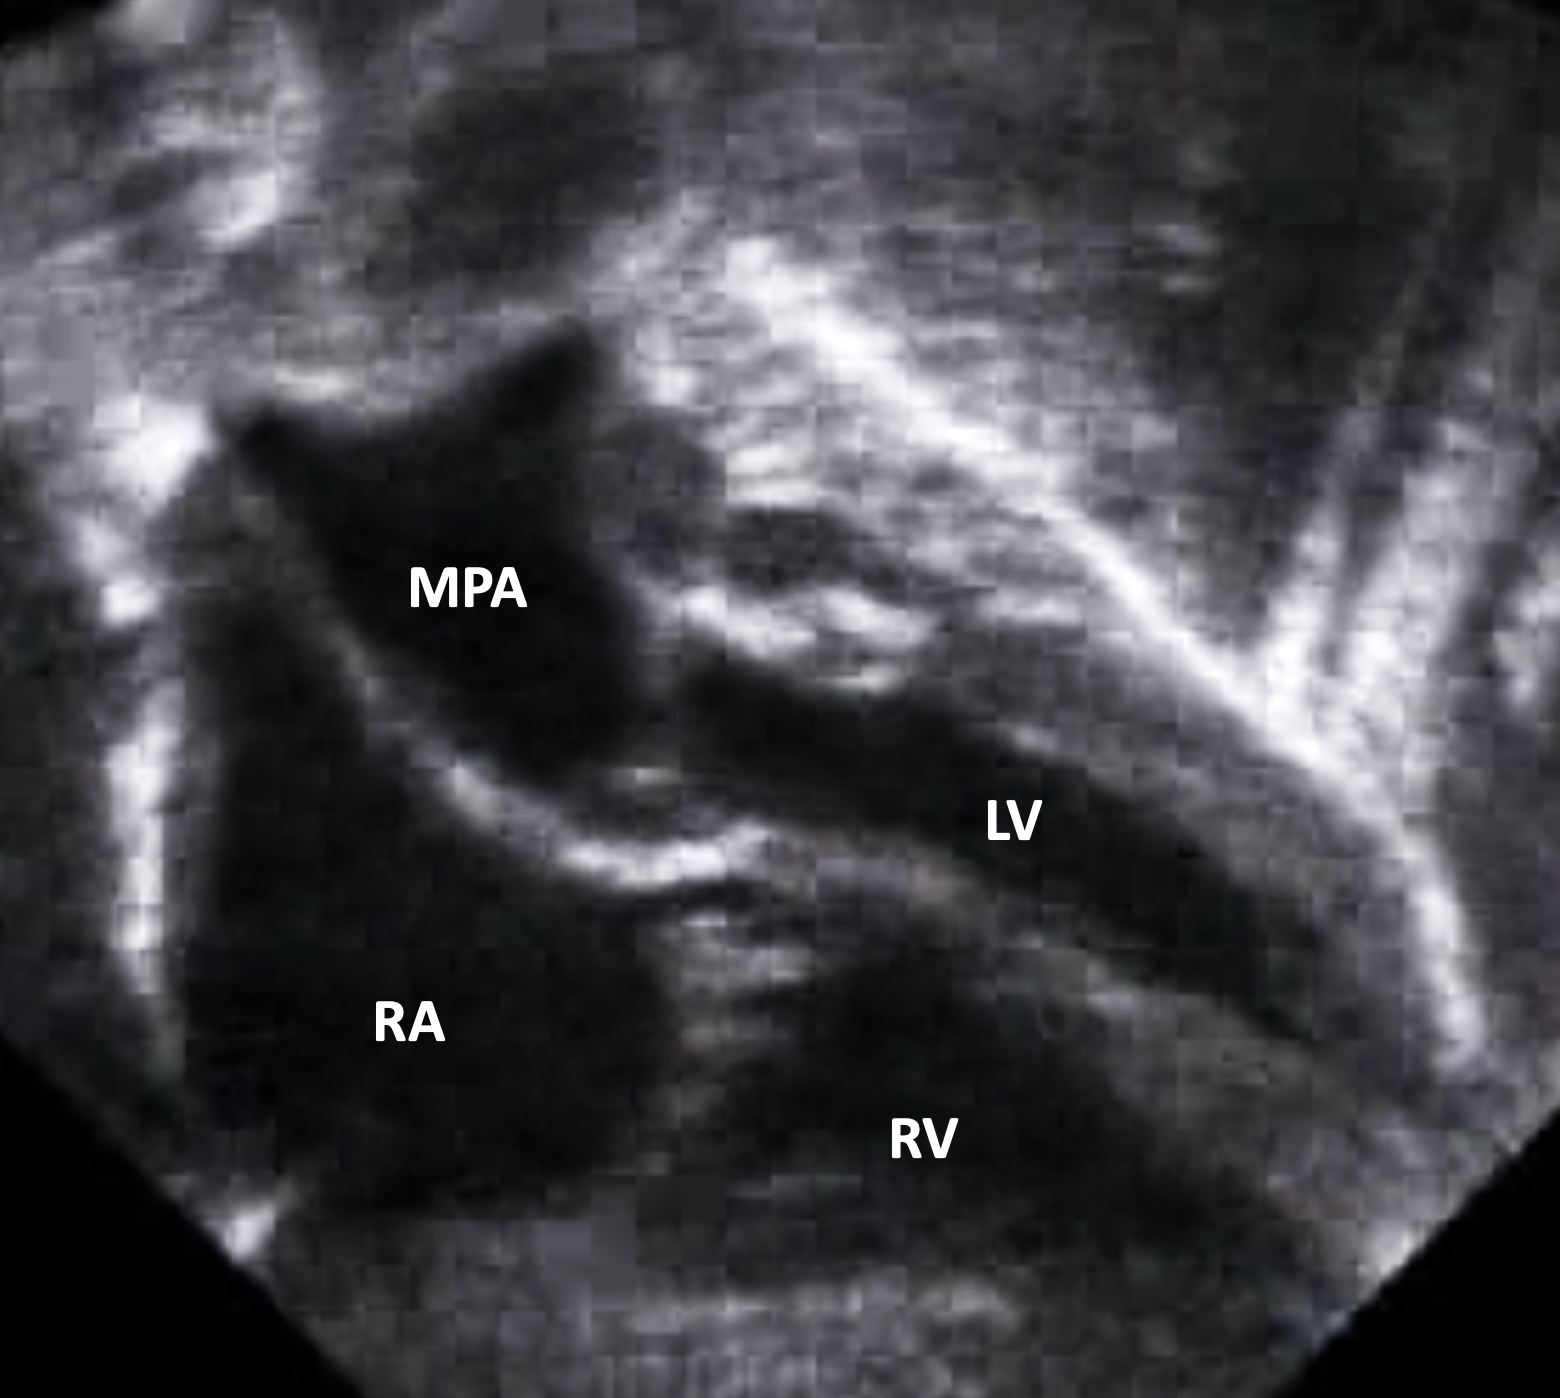

A congenital cardiovascular malformation in which the morphologically right atrium connects to the morphologically right ventricle, the morphologically left atrium connects to the morphologically left ventricle, the morphologically right ventricle connects to the aorta, the morphologically left ventricle connects to the pulmonary trunk, and a ventricular septal defect is not present.

Echocardiogram